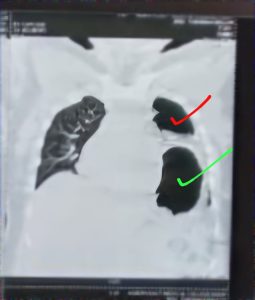

To support the X-ray, a CT chest done . CT report was as same as X ray. In some section of the CT scan lung tissue was totally absent and in some section lungs was confined only in apical region.

Bed side USG of chest shows decreased sliding movement in upper and mid zone in left lung, On rt side sliding movement was normal.a, but absent in lower zone. On rt side normal sliding movement.

Finally it was diagnosed as a diaphramatic hernia. Intestinal loops entered into the thoracic cavity and trapped. So her abdomen became distended, lung tissue compressed to the upper zone the left side.